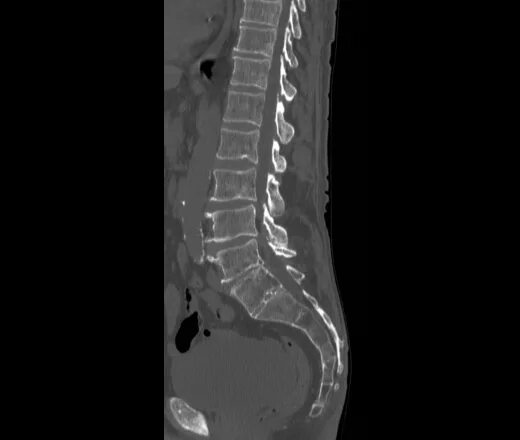

4 стадия метастазы позвоночника